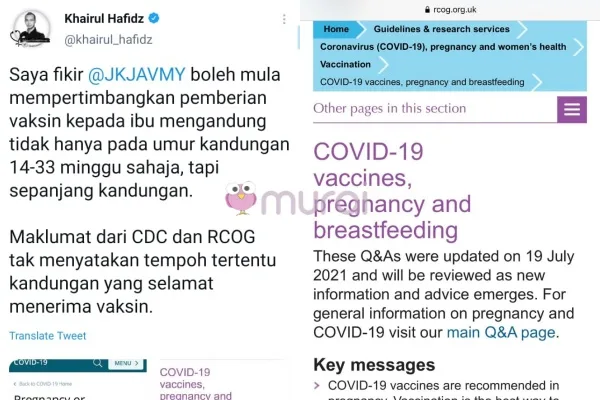

Doktor Khairul juga berharap Kementerian Kesihatan dapat pertimbangkan pemberian vaksin kepada ibu mengandung, tidak terhad kepada usia kandungan 14-33 minggu sahaja tetapi sepanjang usia kandungan berjalan.

“Saya fikir @JKJAVMY boleh mula mempertimbangkan pemberian vaksin kepada ibu mengandung tidak hanya pada umur kandungan 14-33 minggu sahaja, tapi sepanjang kandungan.

Maklumat dari CDC dan RCOG tidak menyatakan tempoh tertentu kandungan yang selamat menerima vaksin.” Ciapnya lagi